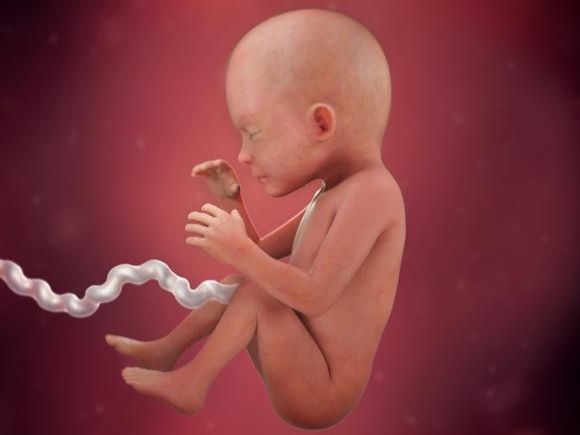

Placenta a její vliv na plod

Plodové lůžko neboli placenta poskytuje děťátku v děloze vše potřebné .

Zásobuje především miminko živinami a kyslíkem. Placenta...

30. týden těhotenství

Maminka

Milá maminko, právě jste v posledním trimestru Vašeho těhotenství. Vaše miminko je teď velmi pohyblivé a během dne budete...

29. týden těhotenství

Maminka

Milá maminko, právě jste v posledním trimestru Vašeho těhotenství. Vaše miminko je teď velmi pohyblivé a během dne budete...

28. týden těhotenství

Maminka

Tímto týdnem vstupujete do posledního, třetího trimestru těhotenství. V posledním trimestru maminky přibírají kolem pěti...